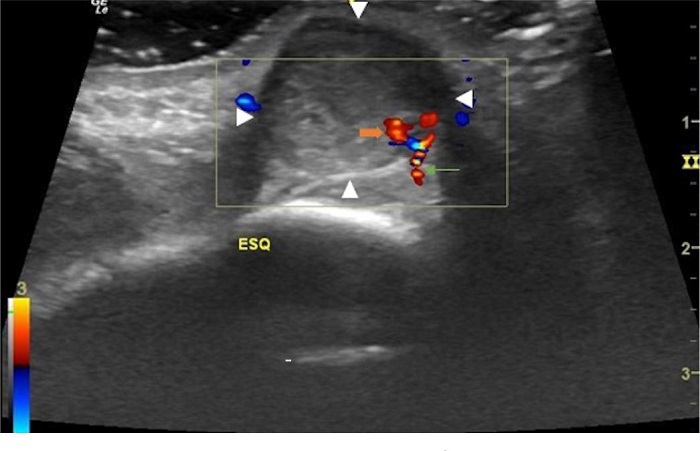

O hematoma à direita apresentava ecotextura heterogênea e media 2,9 x 1,4 x 2,2cm. No interior deste nódulo, destacava-se outro nódulo anecoico, de limites bem definidos, medindo 0,7 x 0,7cm, que apresentava fluxo bidirecional ao exame com Doppler colorido, fluxo alimentado pela artéria supratroclear direita que, por sua vez, localizava-se superficialmente na periferia do hematoma (distando 0,3cm da epiderme) (Figura 5). À esquerda, o hematoma apresentava ecotextura mais homogênea em relação ao lado contralateral, media 2,2 x 1,3 x 1,8cm, e a artéria supratroclear esquerda localizava-se profundamente (distando cerca de 1,0cm da epiderme) na periferia do hematoma.

Junto à artéria supratroclear esquerda, observou-se pequeno nódulo, medindo 0,2 x 0,2cm, com fluxo bidirecional ao exame com Doppler colorido (Figura 6). A visualização das imagens nodulares junto às artérias, associada à presença de fluxo colorido bidirecional ao Doppler (sinal do yin-yang), levou ao diagnóstico de pseudoaneurisma de artérias supratrocleares.